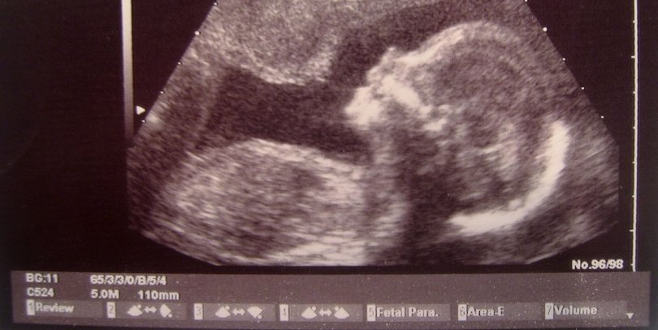

New York Post’ta yer alan habere göre; Haziran 2015’te evlenen Ashleigh ve Bliss Coulter çifti, bebek sahibi olabilmek için çok sayıda doktora gitti. Doktorlardan bir tanesi birlikte bebek sahibi olabileceklerine dair umut verdi. Biyolojik olarak yalnızca bir anne hamileliği yaşayabiliyorken, yapılan bir uygulamayla hem Ashleigh hem de Bliss bebeklerini bedenlerinde taşıdılar.

İki Taraflı Zahmetsiz Tüp Bebek (ER-IVF) adı verilen deneysel yöntemle her ikisi de döllenme sonrası oğullarını fiziksel olarak bedenlerinde taşıdı.

Bir donörden sperm alındı. Bliss’in döllenen yumurtası, kuluçka makinesi yerine Bliss’in rahminde ilk oluşum sürecini tamamladı. Beş gün sonra da bebek hormon terapisi alan Ashleigh’e nakledildi.

Stetson adı verdikleri oğulları, herhangi bir sorun yaşanmadan dünyaya gözlerini açtı.